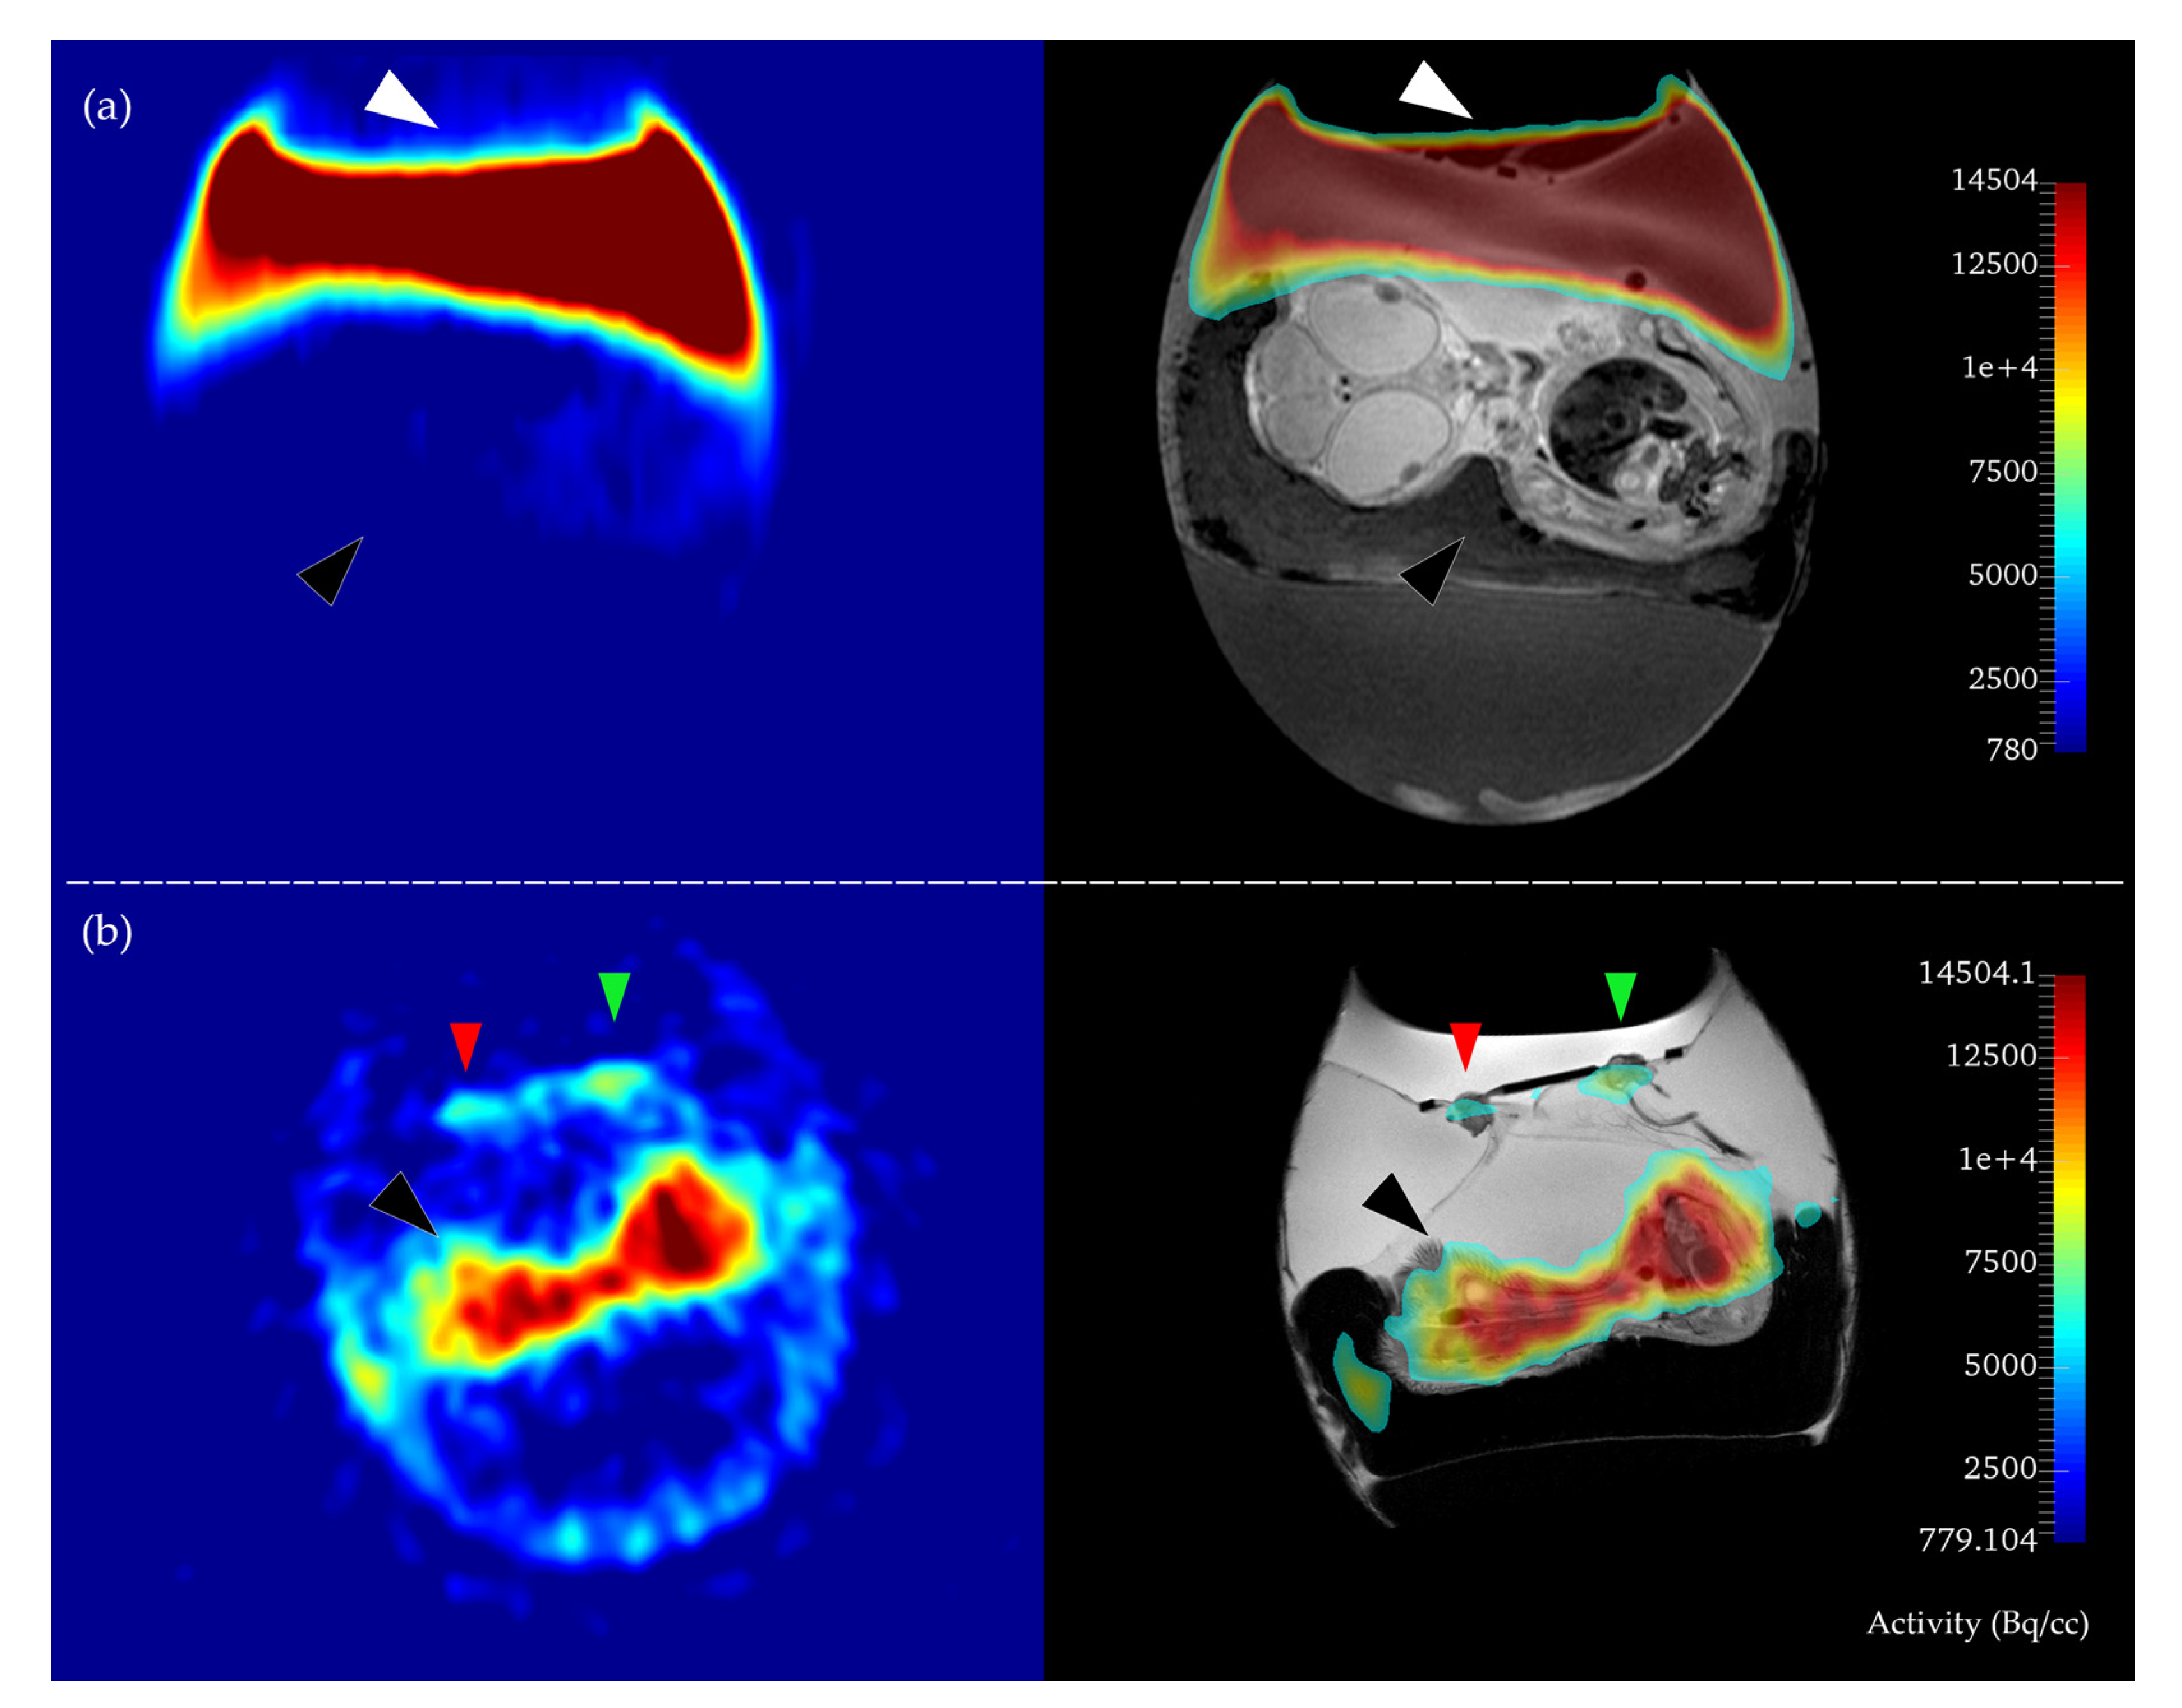

2.2. In Ovo MR and PET Imaging